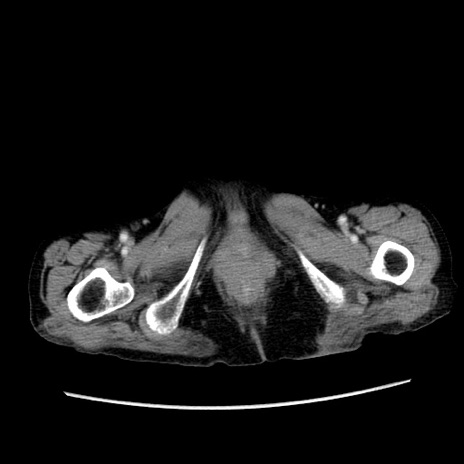

冠状断像